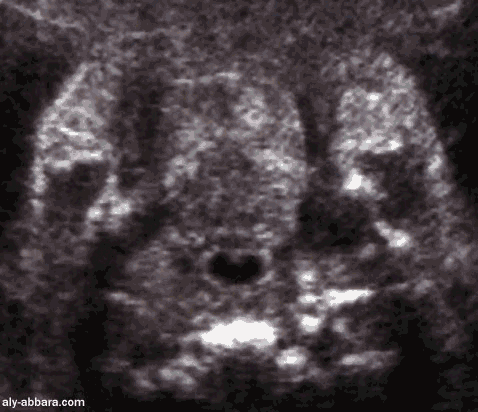

Aspect échographique de langue et la cavité buccale chez

un fœtus de 35 semaines d'aménorrhée

Coupe coronale traversant la cavité buccale